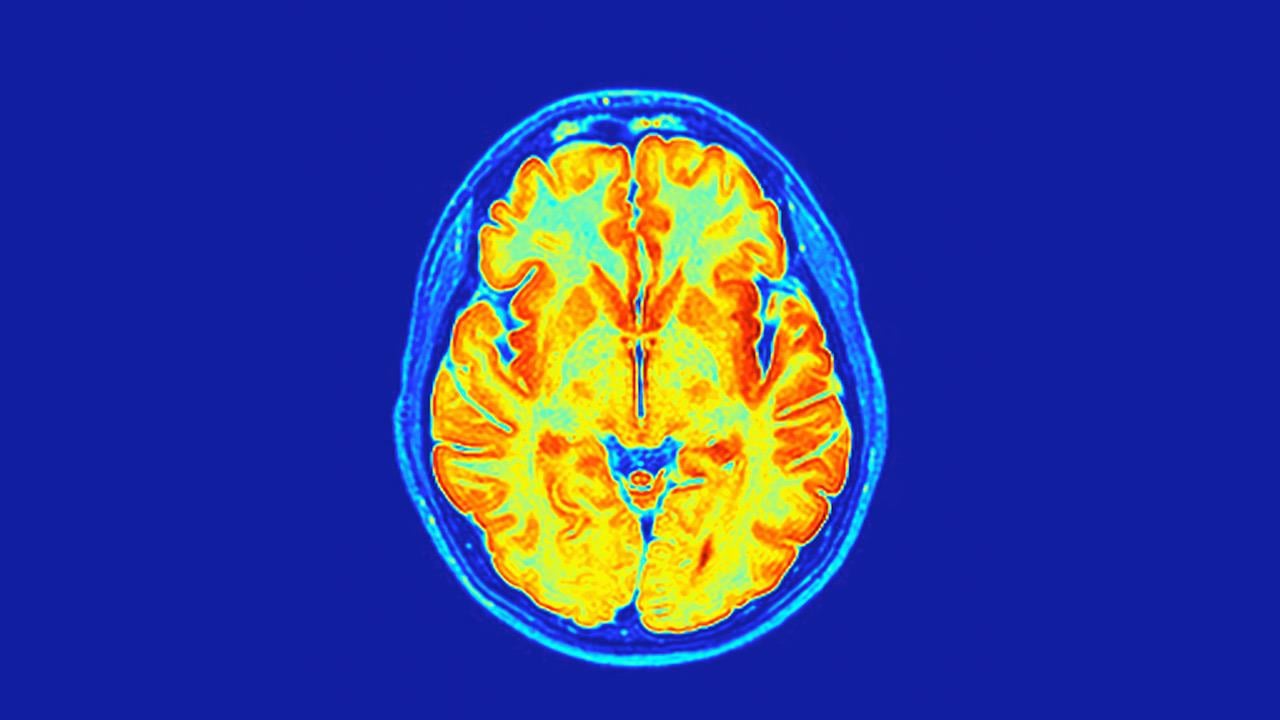

Ερευνητές του Griffith University χρησιμοποίησαν εξελιγμένες τεχνικές MRI για να αξιολογήσουν τις νευρολογικές επιπτώσεις της COVID-19 σε σύγκριση με ανθρώπους που δεν μολύνθηκαν ποτέ.

Η μοναδική μέθοδος μαγνητικής τομογραφίας εντόπισε σημαντικές αλλαγές σε νευροχημικές ουσίες του εγκεφάλου, στην ένταση του εγκεφαλικού σήματος και στη δομή των ιστών σε ανθρώπους με Long COVID αλλά και σε αυτούς που θεωρούσαν ότι είχαν αναρρώσει πλήρως.

Η μελέτη ανέφερε επίσης ότι αλλαγές στον ιστό του εγκεφάλου συνδέονταν με την ένταση των συμπτωμάτων σε ανθρώπους με Long COVID, υποδεικνύοντας ότι ο ιός μπορεί ενδεχομένως να αφήσει σιωπηλή, διαρκείας επίδραση στην υγεία του εγκεφάλου.